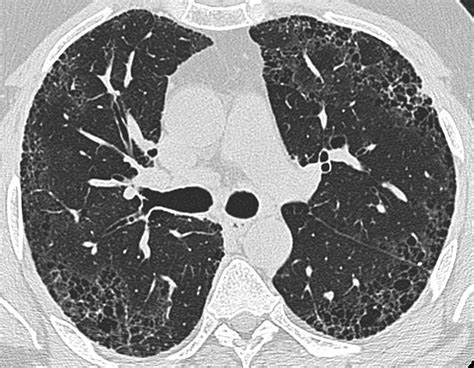

答:主流医学认为,肺纤维化一旦确诊平均生存期为3-5年,也有存活10年以上者,少数急性型病例进展急剧,多在6个月内死亡。 但是经过我们的临床观察,凡是系统接受新鲜中药特色疗法治疗的患者,95%以上都有好转,大量患者症状减轻、肺部CT逆转,部分患者肺部CT完全逆转,达到临床痊愈。 临床痊愈的患者再经过一段时间的巩固治疗后,肺纤维化复发的几率明显降低,寿命可与正常人无异。